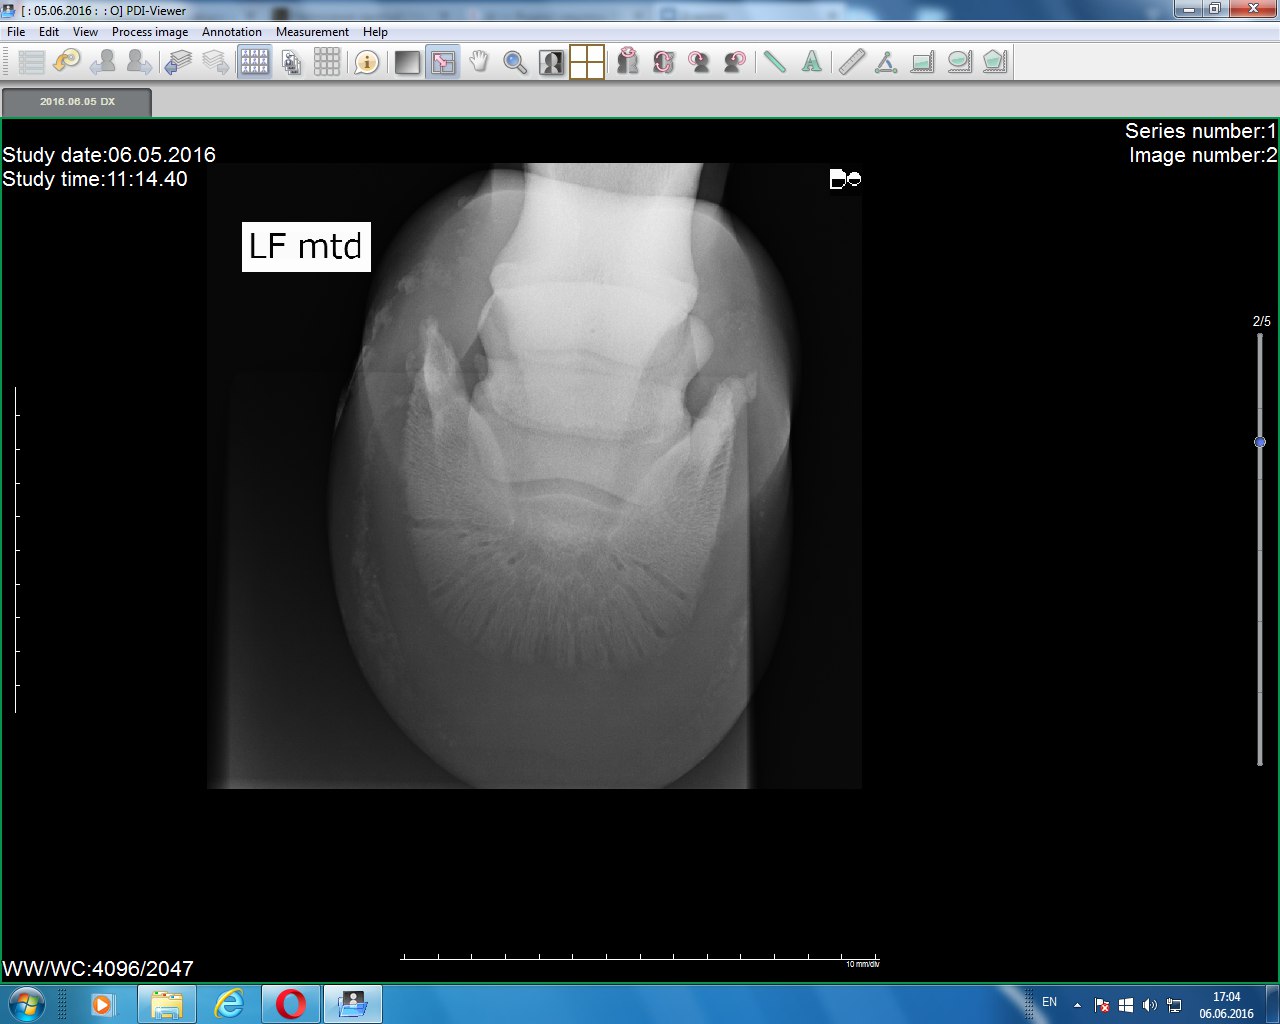

Левый перед(2016) Не обращайте внимание на обозначение, переснимали после правой ноги. и забыли изменить